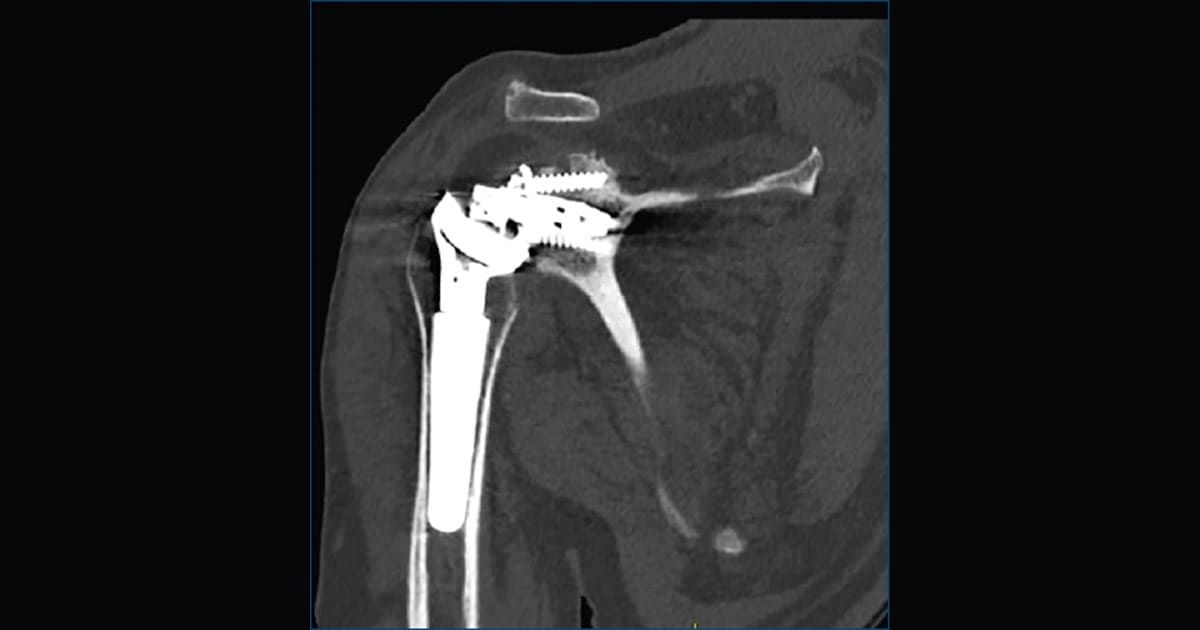

Il caso clinico: cosa insegna alla pratica ortopedica

Nel caso pubblicato, un paziente sottoposto a RTSA ha sviluppato instabilità ricorrente e ripetute mobilizzazioni della glenosfera. Nonostante un primo intervento di revisione, la problematica è riapparsa dopo un trauma, fino a richiedere una seconda revisione.

L’esito intraoperatorio ha evidenziato:

• rottura dell’anello di connessione;

• metallosi peri-protesica;

• formazione estesa di tessuto cicatriziale;

• mobilizzazione della vite craniale del baseplate.

La sostituzione dei componenti danneggiati, associata a un’adeguata stabilizzazione, ha permesso di ripristinare funzionalità e ROM.

Radiografie comparative e TC svolgono un ruolo fondamentale nel valutare la posizione della glenosfera e il grado di allentamento della componente.